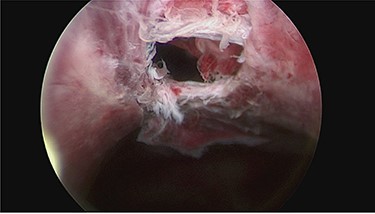

Day 1 post intervention, post-renal kidney injury due to mass effect of haematoma was suspected (creatinine 194 μmol/L and bilateral hydronephrosis on ultrasonographic study). Emergency cystoscopy (for consideration of ureteric stenting) revealed an anterior bladder wall perforation which communicated anteriorly with the haematoma in the extra-peritoneal space (Fig. 3). This was managed conservatively with long-term catheter and bilateral nephrostomy to decompress the dilated upper urinary tracts. Following 1 week admission in ICU, patient made gradual recovery with no evidence of re-bleeding following reintroduction of anticoagulation, nephrostomy tubes were removed 3 weeks post insertion uneventfully.

Cystoscopy showing perforation in anterior bladder wall communicating with the haematoma.